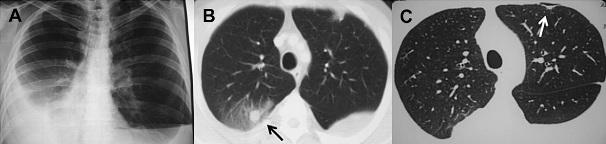

类风湿结节就是类风湿关节炎的关节外表现之一,不少患者在得了类风湿关节炎后出现了各种症状,比如胸部CT显示肺部多发结节,出现一个个“疙瘩”,心中不免有许多猜疑和担忧。事实上,这种疙瘩正和类风湿结节有关,让我们来认识一下什么是类风湿结节。

类风湿结节对患者影响程度取决于疾病结节发生部位,尺骨鹰嘴、前臂、手指和脚跟等关节伸侧受压部位最常见,肺部类风湿结节多见于外周及胸膜下等肺周边部位,直径可以从数毫米到数厘米。少数影响骨髓、声带、心脏瓣膜等重要器官。

多数类风湿结节是固定和无痛的,发生足掌及跟腱等引起明显不适,表浅部位的类风湿结节常根据病史及临床表现不难诊断,肺部及内脏部位类风湿结节需与莫顿神经瘤、结核及肿瘤性鉴别,必要时可能需要病理活检明确诊断。